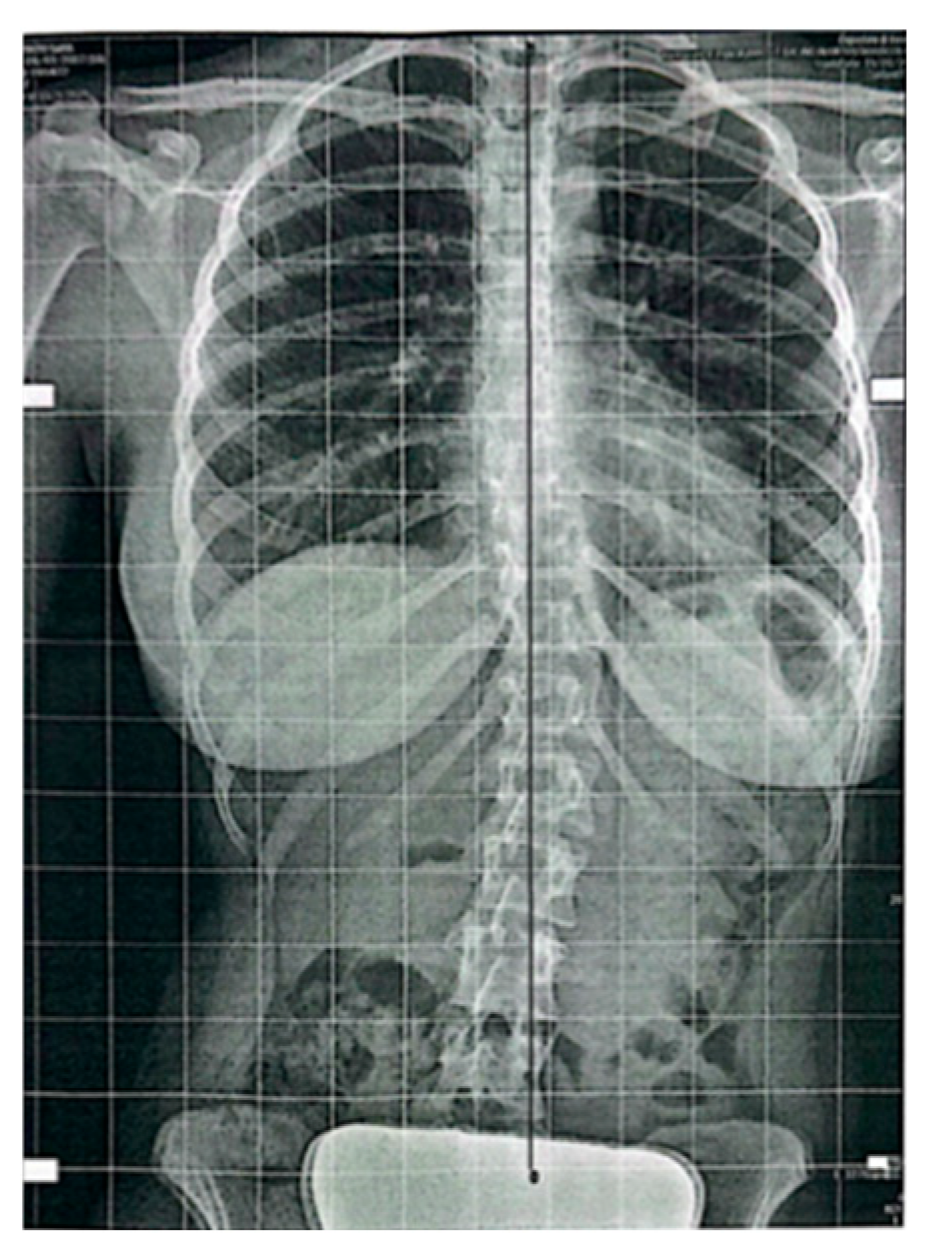

Follow-up standing radiographs showed a clear reduction in coronal plane deviation in both cases. In Case 1, the thoracolumbar Cobb angle decreased from 19.4° at baseline to 4.1° (Figure 3) at follow-up, with a parallel reduction in rotational parameters (DAR from 1.9 to 0.4) and reduced pelvic asymmetry. In Case 2, the Cobb angle decreased from 41.14° to 15.17° (Figure 4), with the DAR decreasing from 3.7 to 1.36 (Table 1). No worsening of sagittal alignment or development of new compensatory curves was observed on follow-up imaging. Radiological measurements were performed by an independent radiologist, and the anonymized radiological report is provided as Supplementary Material S1.

At follow-up, radiographs demonstrated a marked reduction in coronal plane deviation. The Cobb angle decreased to 4.1°, with a parallel reduction in rotational parameters (DAR 0.4). Pelvic asymmetry was reduced compared with baseline, and no worsening of sagittal alignment was observed.

Figure 3. Case 1: Follow-up standing anteroposterior spinal X-ray showing a marked reduction in thoracolumbar curve (Cobb angle 4.1°).